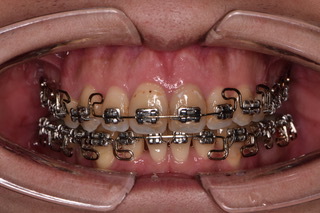

経過をご覧ください。

同じく、矯正器具とゴムを使って改善を図りました。

正面においては、真ん中がぴったりと揃い、前歯も閉じているのが分かります。

側面においては、上の前歯は下がり、下の顎が前方に誘導されているのも確認出来ます。